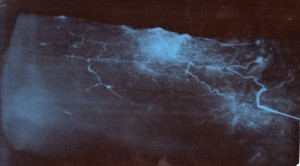

Особенности зоны, кровоснабжаемой из перфорирующей ветви малоберцовой артерии исследовались нами посредством проведения рентгенангиографии на патоморфологическом материале. Были исследованы 16 препаратов лоскутов. Учитывая территорию кровоснабжения исследуемой ангиосомы, которая составляет максимально до 18 см в длину и до 9 см в ширину, кожно-фасциальный лоскут препарировался в несколько больших границах (+ 3 см в длину и ширину), но не выходя за пределы гребня большеберцовой кости [4]. Выделенная перфорантная ветвь малоберцовой артерии зондировалась канюлей на глубину 2-4 см, при затруднении проведения канюли, её проводили по металлическому проводнику 0.014 inch. После этого на артерию поверх канюли накладывался турникет, и герметизировали сосуды по периферии лоскута путем наложения лигатур или методом электрокоагуляции (рис. 2). В ходе подготовки сосудов к контрастированию они промывались раствором гепарина (5 000 Ед / 100 мл). Сосудистое русло заполнялось под давлением йод содержащим контрастным веществом (Ультравист – 370; Визипак – 320), производились рентгенангиографические снимки в нескольких фазах наполнения. С целью определения размеров зоны с устойчивым кровоснабжением от перфорантной артерии (ангиосомы) и её индивидуальной вариабельности, проводили планиметрическое исследование с определением возможных размеров формирования лоскута (рис. 3).

Рис. 2 А. Выделение перфорантной артерии и взятие патоморфологического материала (кожно-фасциального лоскута); Б. Препарат с зондированной перфорантной артерией и проведенной герметизацией.

Рис. 3. А. Рентгенангиографический снимок препарата надлодыжечного лоскута с визуализацией зоны кровоснабжаемой перфорантом до уровня гребня большеберцовой кости. Б. Условная статистически устойчивая зона кровоснабжения препарата кожно-фасциального латерального надлодыжечного лоскута.

При проведении анализа рентгенангиографических исследований на патоморфологическом материале нами была определена вариабельность размеров возможного формирования латерального надлодыжечного лоскута от 6 до 10 см. в ширину и от 14 до 19 см. в длину. Что зависело от антропометрических параметров трупов и их биологического возраста.